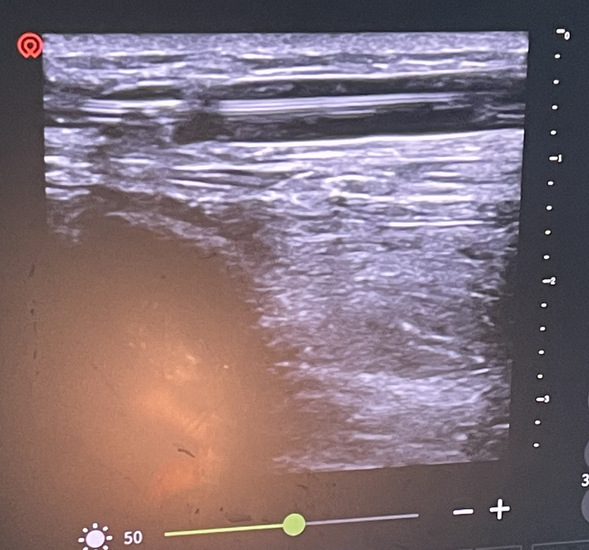

术前超声检查

术前准备工作